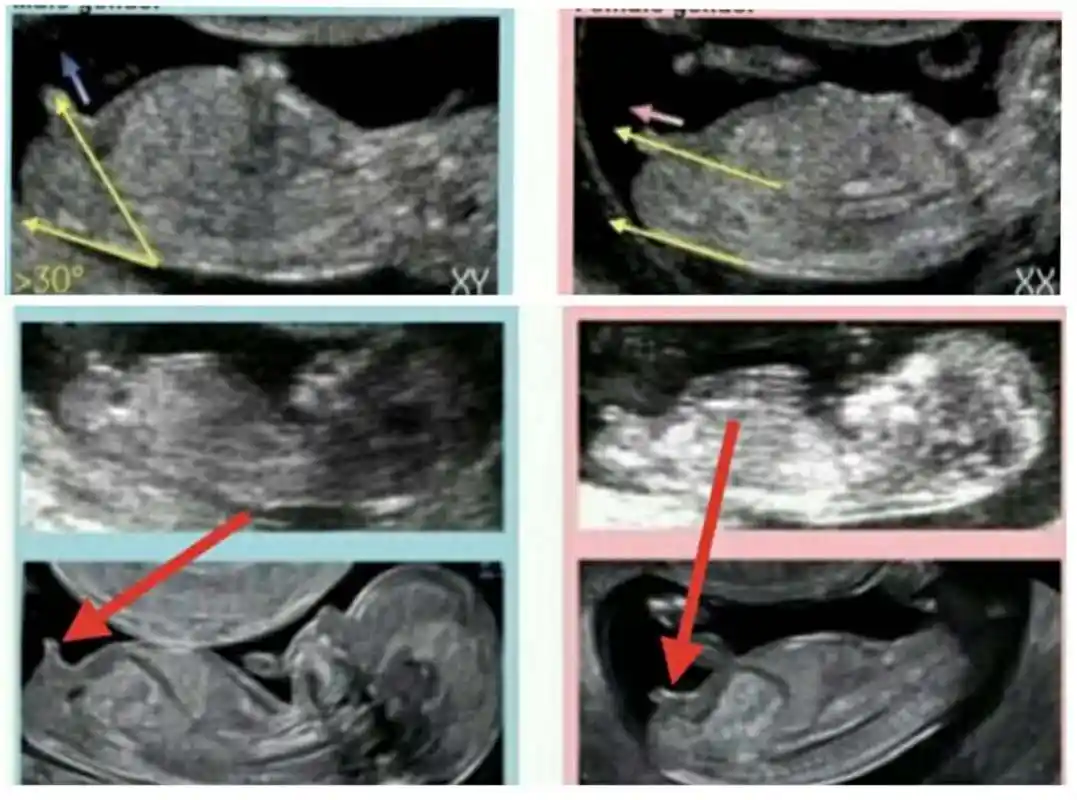

请教下专家,能否看的出三个月的宝宝是男是女?